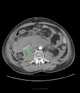

Ruptured aneurysm

An aneurysm is an outward bulging, likened to a bubble or balloon, caused by a localized, abnormal, weak spot on a blood vessel wall. Aneurysms may be a result of a hereditary condition or an acquired disease. [Source: Wikipedia ]